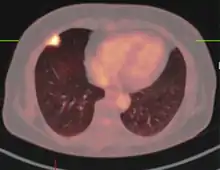

PET-CT of a tuberculoma

The appearance of a tuberculoma on imaging can vary according to the composition and age of the mass. They may appear as either non-caseating or solidly caseating lesions.[20] Initially, tuberculomas appear hypodense on computed tomography (CT) scans with significant surrounding edema.[23][3] The "target sign" is pathognomonic for tuberculoma on CT, with a nodular ring-enhancing mass and central calcification.[24][20] The characteristic ring-enhanced appearance is due to lack of blood supply in the central necrotic core that is visualized with injected contrast.[22] Sometimes a hypodense central area is seen instead of calcification.[25] When considering other potential intracranial masses in a differential diagnosis, such as cysticercosis, pyogenic abscess, and neoplastic lesions, tuberculoma can be identified by its larger size (>2 cm), edema, and irregular border.